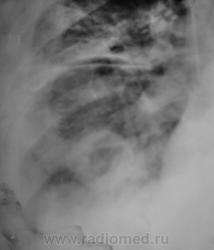

У пациента КТ не на диске, а распечатка. Вот и представляю так. как перефотографировал. Какое мнение будет уважаемые коллеги?

Валентин Львович! Мне думается, что распечатка КТ на бумаге сама по себе уже не информативна и не предназначена для диагностики. Смысла ее перефотографировать абсолютно не имеется.

Но все таки абсцедирующая пневмония!

ИМХО: впечатление о значительной положительной динамике создаётся, на мой взгляд, по причине уменьшения объёма выпота в плевральной полости,вероятно потому, что в последней стоит катетер.Тень абсцесса хоть и стала меньше, но имеет ещё большие размеры.По КТ абсцесс виден и в нижнем поле левого лёгкого; картина самих абсцессов, их множественность, быстрое развитие( через 3 дня после оперативного вмешательства), вызывает подозрение на эмболию легочной артерии( о чём уже говорили коллеги из области).

согласен с ТЭЛА. На КТ подобное видел - субплеврально, полость деструкции с бронхо-сосудистым тяжем к корню легкого, жидкость в плевр полости, быстрая динамика...